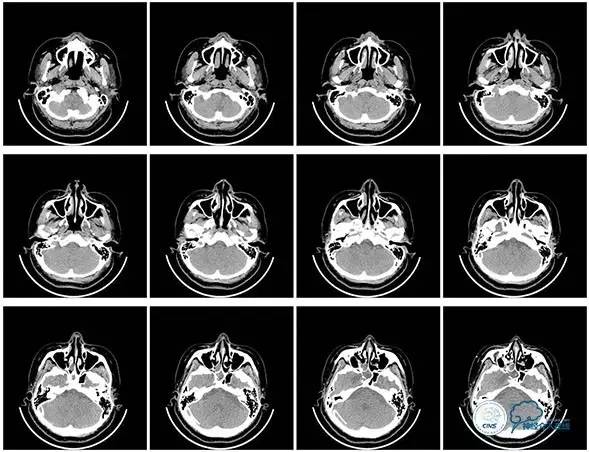

2016-06-03 CT

2017-06-07 CT

术后头颅CT